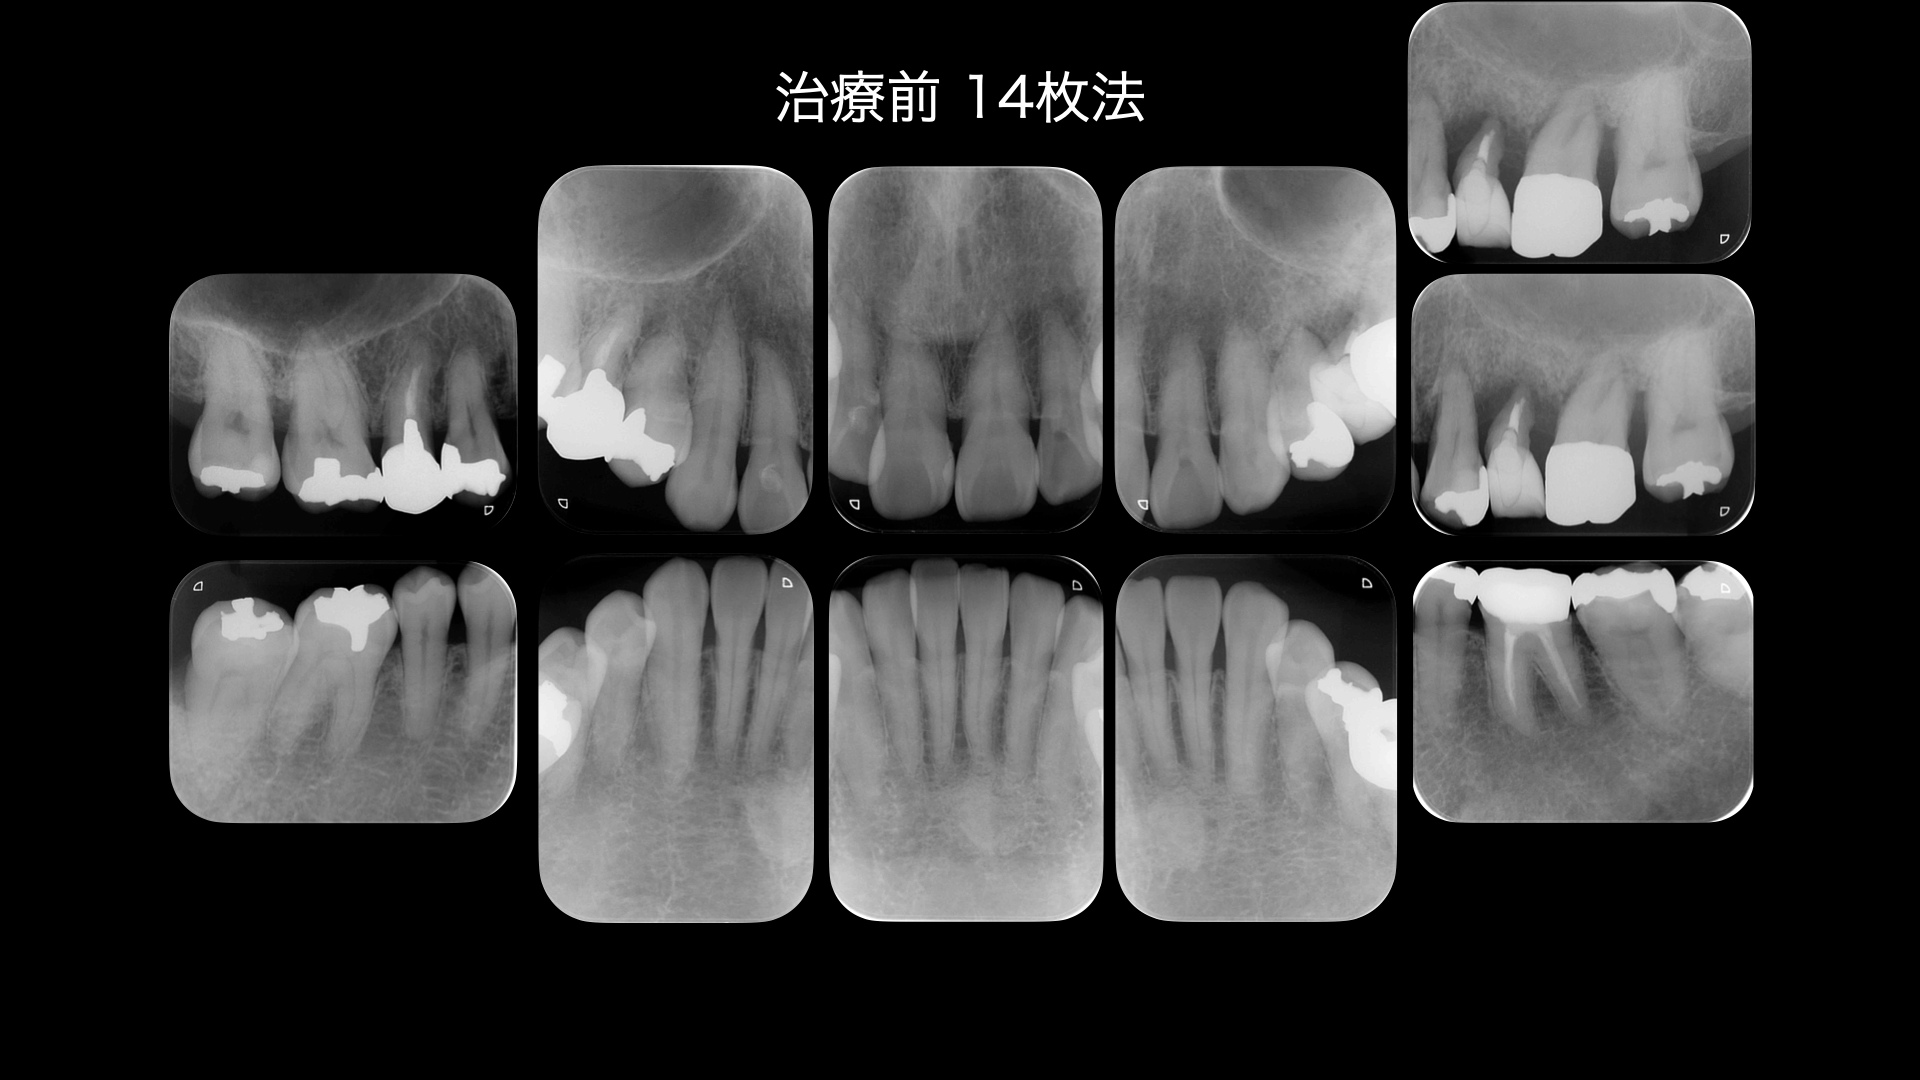

歯周病の検査です。やや全体的に歯周病が進んでいますが、特に左上の部分は顕著にすすんでいます。

矯正の診断をおこないました。

そこで矯正をせずに前歯を噛ませるにはどうしたらよいか。模型上でシミュレーションをしました。

すると、茶色のwaxの部分は足しているところで、鉛筆の斜線は削っているところです。

下の前歯はほとんど足す必要があり、多くの歯を治療しなければいけません。

どうしても全体的な矯正治療(平均2〜3年)を望まれなかったので、模型上で咬合調整をおこない、やや前歯が噛み合うところまで調整すると矯正治療期間が短くなります。

模型上で、そこから歯を並べて(排列)みて奥歯をさわらずに短い期間で矯正治療ができるのかをシミュレーションした結果

可能ということがわかったので、この計画にしました。